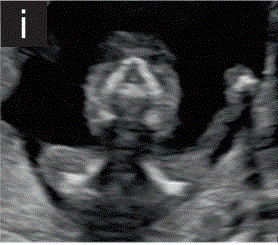

4.4在横断或冠状位切面中,应尝试通过眶间距离和鼻后三角来显示眼睛,以显示上颌骨和下颌骨(图2h和2i)。

图2 11+0至14+0周时,可作为详细胎儿超声检查的一部分获得的解剖图。

(h) 胎儿头部的横断切面视图,显示眼眶和晶状体、上颌突和鼻。

(i) 胎儿面部的斜冠状切面显示眼眶和鼻后三角,包括鼻骨、上颌突和前上颌骨的牙槽嵴。在这个平面上也可以看到下颌间隙。